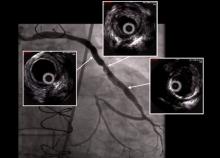

Gianni Angelini of Imperial College, London, United Kingdom, discusses early, intermediate, and late vein graft failure and surgical techniques to improve vein graft patency rates at all stages.